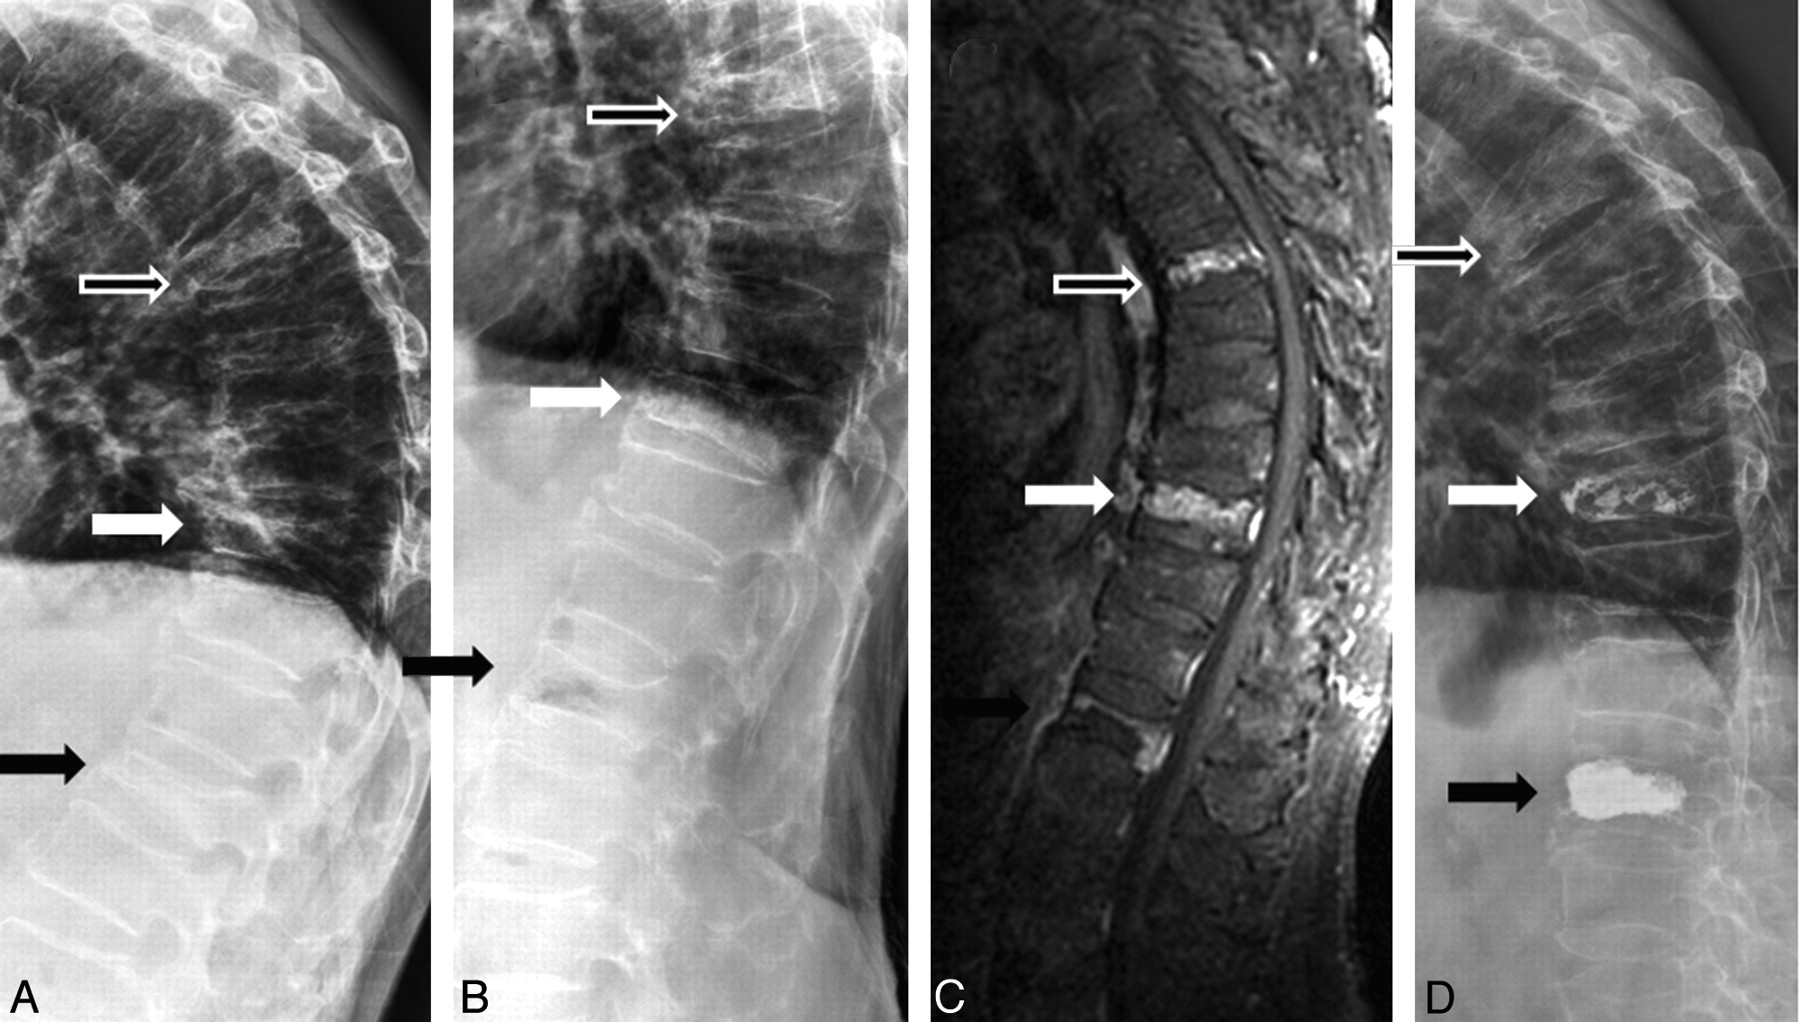

In this study, 87.5% of 144 MR imaging−proved edematous VCFs were demonstrated to be mobile. The sensitivity of dynamic radiographs in diagnosing the MR imaging−proved edematous VCFs is 0.87. However, in patients with painful VCFs that need vertebroplasty or surgical intervention, 99% of patients can be shown to have at least 1 mobile VCF. The sensitivity of dynamic radiographs in diagnosing the painful vertebrae in patients with severe pain is 0.99. An explanation is that not all edematous vertebrae are mobile; however, in patients with severe back pain who need vertebroplasty or surgical treatment, there is always at least 1 mobile vertebra. Toyone et al8 demonstrated a significant correlation between back pain and changes in the wedging rate from a supine to standing position. Changes in the wedging rate of >10% were always associated with more severe back pain. If the vertebrae are edematous but not mobile, the pain severity should be lower. So in a patient with mobile and nonmobile MR imaging−proved edematous VCFs, the mobile VCF should be the major pain source. In this study, 1 patient had 3-level compression fractures: 1 mobile and 2 nonmobile. We only treated 2 vertebrae (1 mobile and 1 nonmobile), and he still experienced dramatic pain improvement (Fig 3).

A 74-year-old man with severe back pain due to T6, T10, and L1 compression fractures. A and B, Sitting (A) and supine with bolster (B) lateral radiographs show mobility at L1 (black arrow) but no mobility at T6 (hollow arrow) and T10 (white arrow). C, Contrast-enhanced T1-weighted MR image demonstrates contrast enhancement at T6, T10, and L1. D, Postvertebroplasty lateral radiograph shows cement filling in T10 and L1. Vertebroplasty was not performed at T6, but the patient still showed dramatic improvement.

Because MR imaging can provide an accurate diagnosis, what is the role of dynamic radiographs? In the time that elapses between the initial MR imaging evaluation and vertebroplasty, it is possible for additional fractures to occur. Benz et al10 recommended a repeat preprocedural MR imaging obtained within 1 week in select candidates to help ensure that all painful fractures are treated. However, the disadvantages of preprocedural MR imaging include the time, expense, and demands on the radiology department. Because dynamic radiographs are sensitive in diagnosing the painful vertebrae, they can be used as a preprocedural re-evaluation examination to rule out any new lesions if MR imaging was not recently performed. The dynamic radiographs will be more valuable in patients who cannot undergo MR imaging. In addition to its diagnostic value, dynamic radiographs can help interventionalists estimate the postprocedural vertebral height and shape and cement injection area and amount. It can also help interventionalists assess the feasibility of vertebroplasty in the vertebral plana (Fig 1, black arrow).